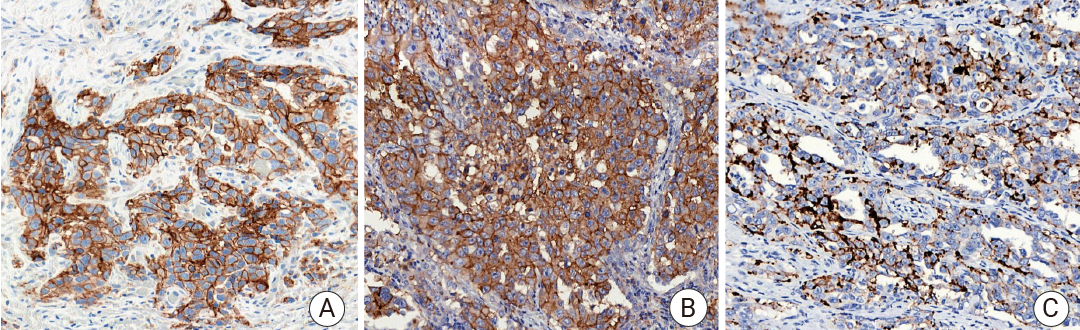

免疫组织化学 (IHC) 常用的肿瘤标志物_MCE 中国

Section.01肺癌标志物 PD-L1PD-L1—— 免疫检查点分子,属于 B7-CD28 免疫调节超家族。定位: 细胞膜。功能: PD-L1 是一种跨膜蛋白。其主要生理功能是在免疫突触中与免疫 T 细胞表面的 PD-1 受体结合,传递抑制性信号,通过抑制 T 细胞活化和增殖来发挥作用。肿瘤细胞或肿瘤微环境中的免疫细胞会高表达 PD-L1,与浸润 T 细胞的 PD-1 结合,从而“关停” T